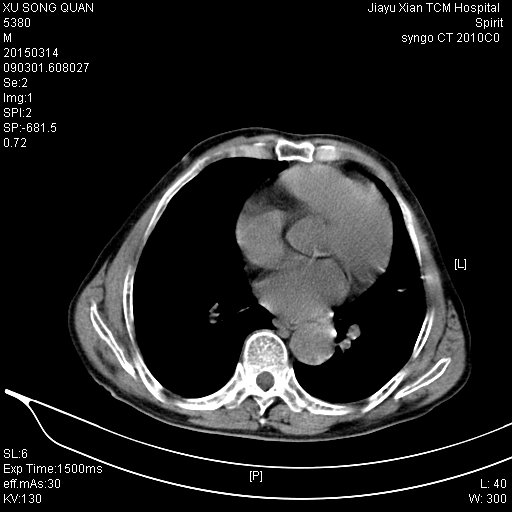

CT50056:男.79岁.腹部不适

请各位老师看看

结石并积水

积水

结石合并积水,不除外囊肿